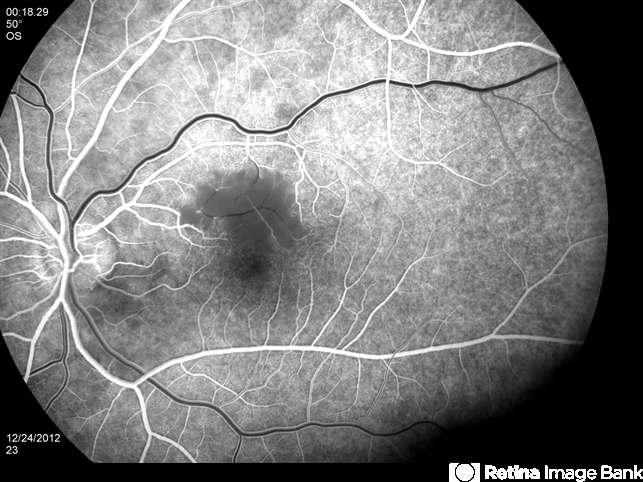

- BRAO dt cat scratch disease in a young patient

- cat scratch retinitis, branch retinal artery occlusion (BRAO)

- A 38-year-old male complained of a grey spot in visual field in his left eye. On clinical exam BRAO in LE, confirmed by FA, as seen in picture. Image shows delayed filling of artery. Serology for bartonella was positive.